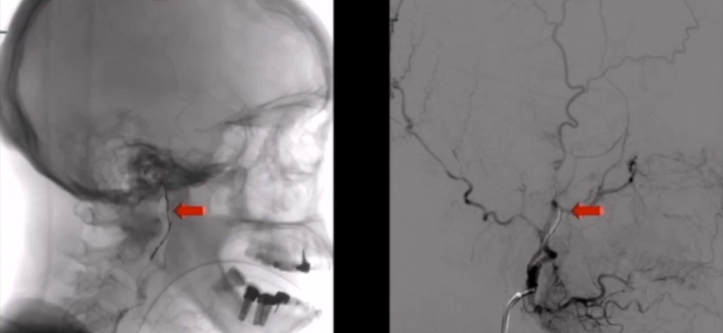

第二步是术前血管栓塞:在正式手术前,经介入手段在咽升动脉处置入栓塞线圈,提前切断肿瘤供血来源,大幅压缩术中出血量,为后续操作争取更充裕的术野空间。